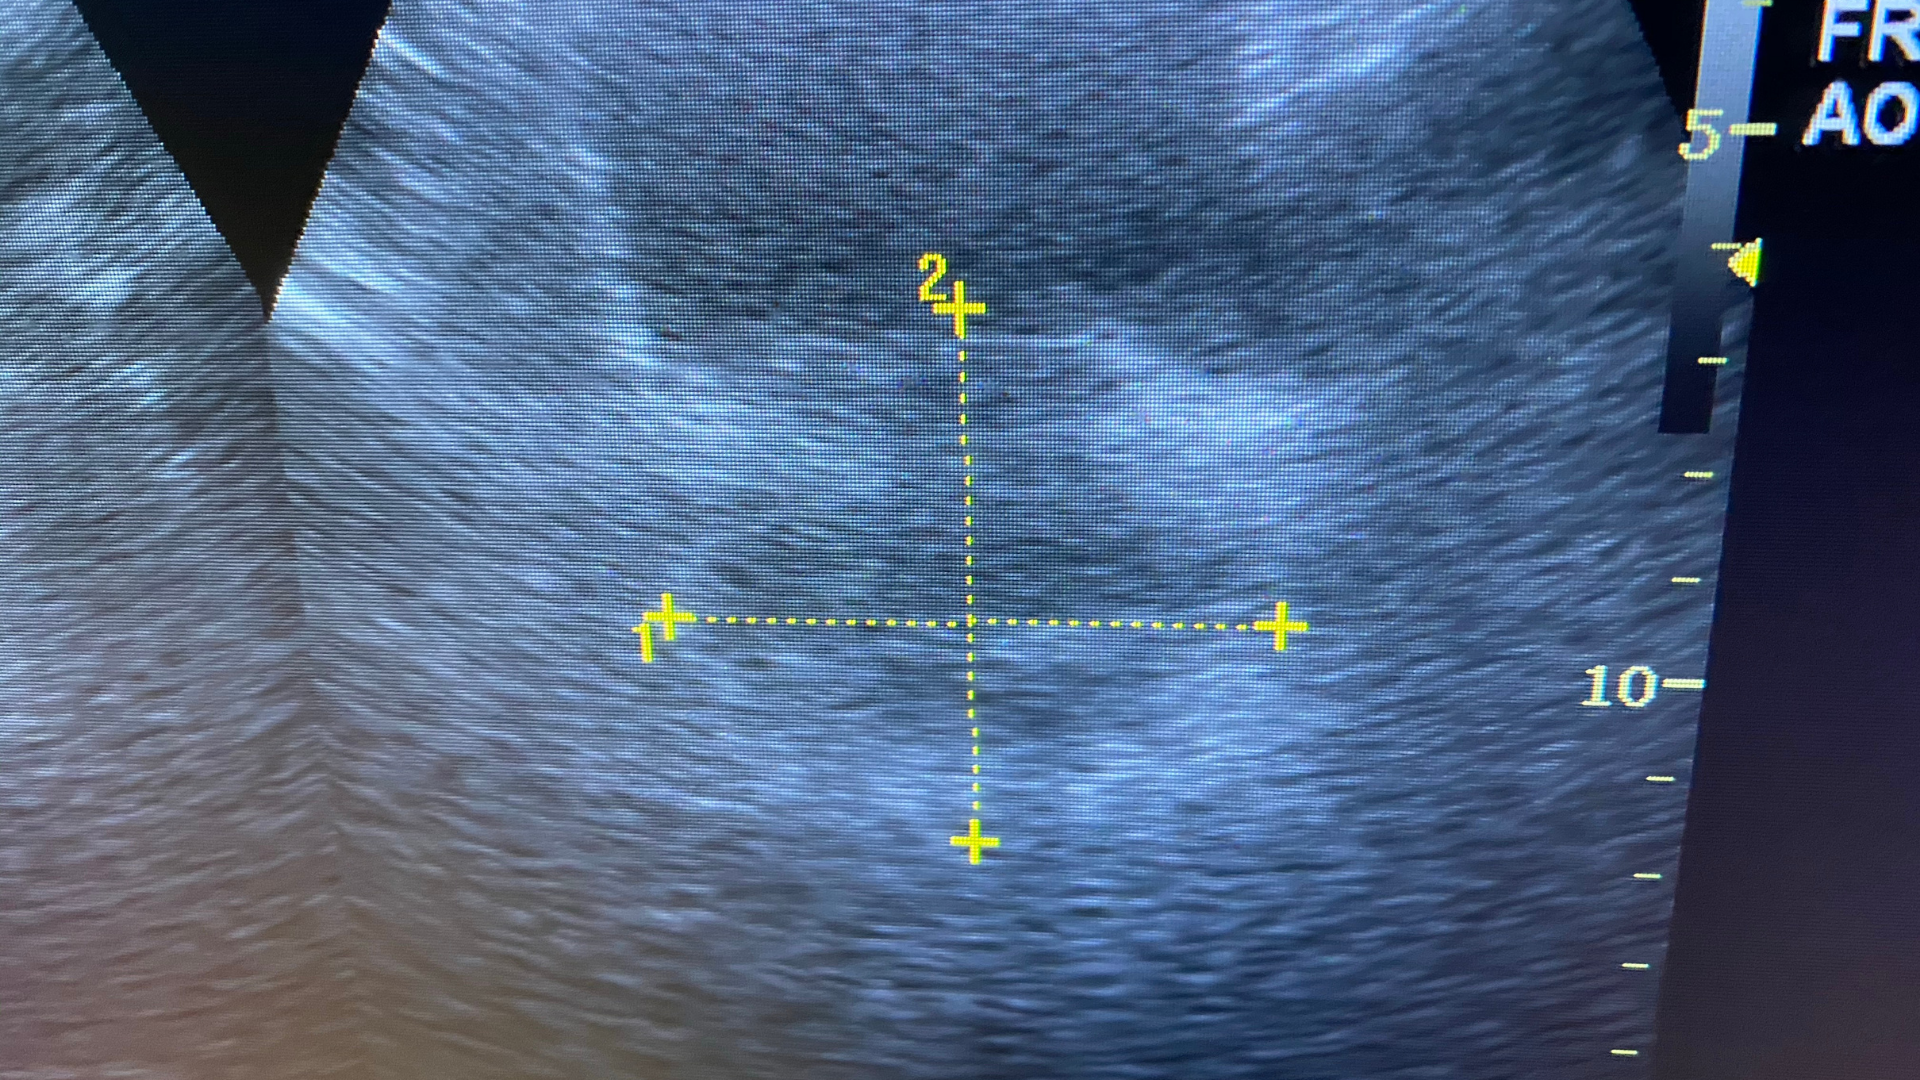

- Siêu âm: Xác định kích thước tuyến tiền liệt và lượng nước tiểu tồn dư sau khi đi tiểu.